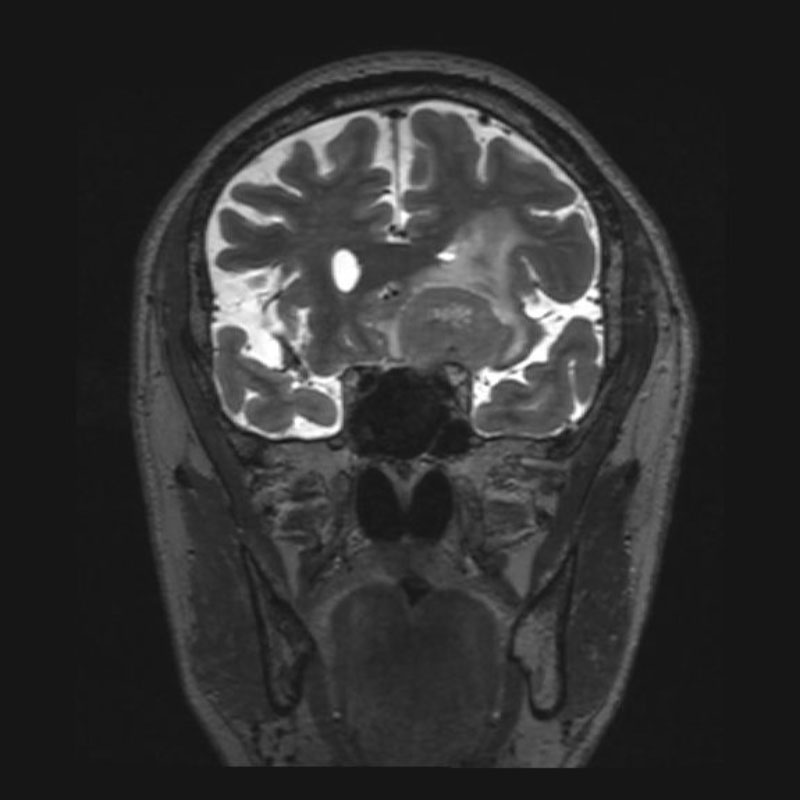

断層撮影

No.’25_108 手術前1

No.’25_108 手術前2